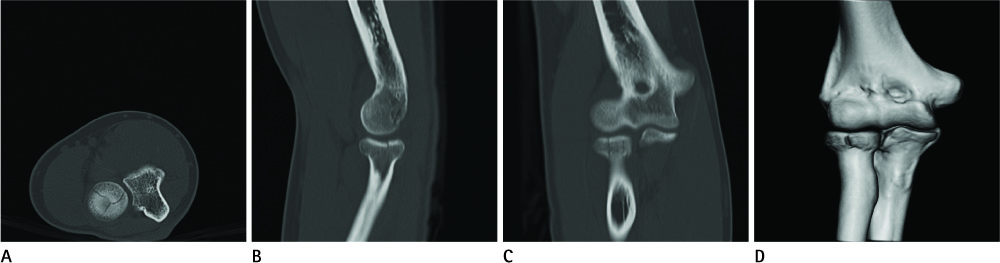

Diagnostic Value of Multidetector Computed Tomography in Radial Head or Neck Fractures

To evaluate the diagnostic value of multidetector computed tomography (MDCT) in radial head or neck fracture, and to evaluate factors that affect MDCT image quality.

Sixty-six radial fractures in 65 patients, who underwent both radiography and MDCT, were included. Detection of fracture and classification of types were recorded for each modality. Patients were divided into the good (A) and poor (B) image quality groups, and recorded the factors, such as arm positioning, flexion angle, and cancellous bone density.

The detection rate of fracture showed no significant difference between the two modalities. However, classification of the fracture type was significantly accurate by MDCT (p < 0.0001). Eight cases were only detected on MDCT and three cases were only detected on radiography. Fracture type was discordant in 11 cases. MDCT scanning with raising arm (p < 0.0001), with lesser flexion angle (p = 0.004), and higher cancellous bone density (p = 0.010) showed better image quality.

Radiography is a good primary tool for detecting radial head or neck fracture. However, MDCT can be an additional tool for classifying the fracture type and cases with negative radiographic findings. Arm positioning, flexion angle, and cancellous bone density affect MDCT image quality.